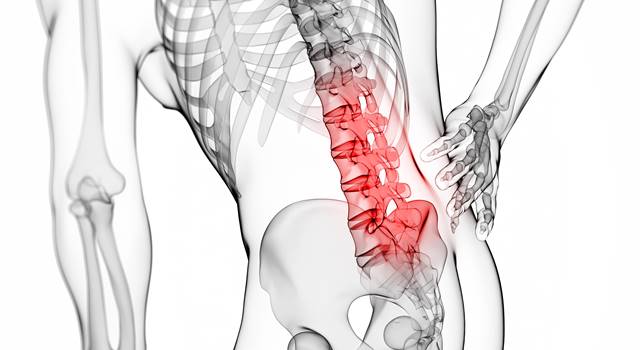

背骨の数は?名前と構造をレントゲンと図でわかりやすく解説します

人間の背骨はいくつあるかご存知ですか? 今回は人間の背骨の解剖について詳しく解説します。この記事を読めば人間の背骨の解剖や構造が理解できて、かなりイメージできるようになります。ぜひ最後までご覧ください。 背骨といえば人間の骨の大黒柱、それ...